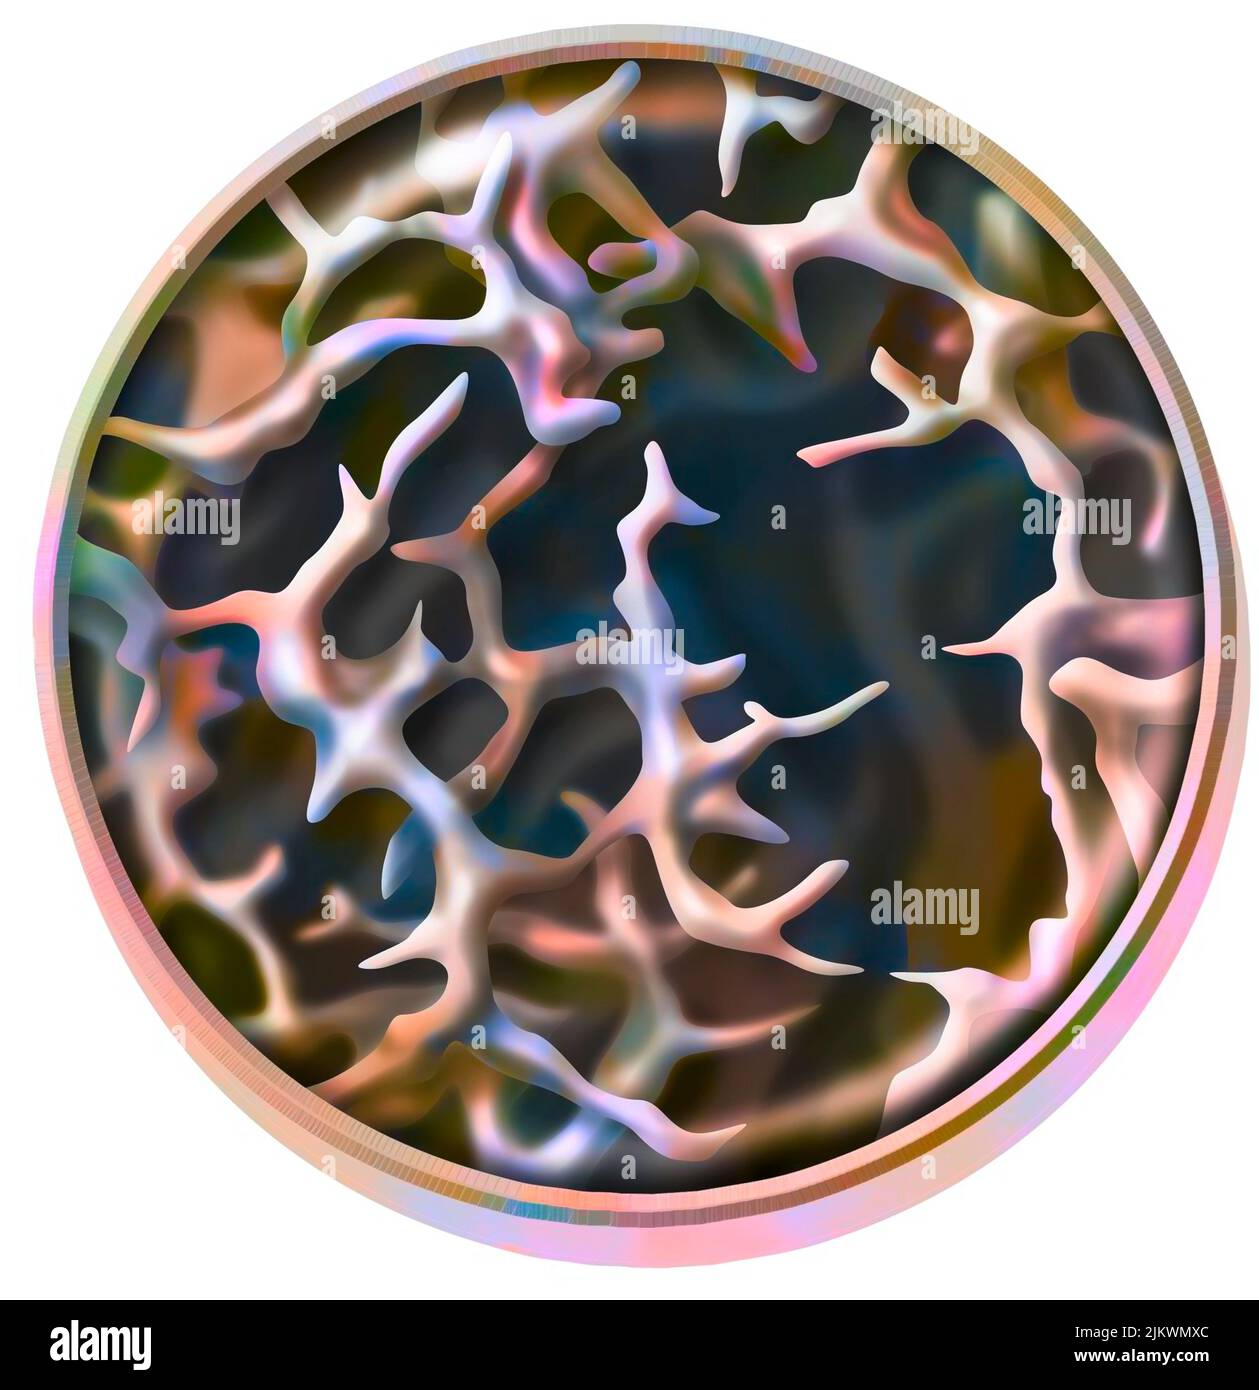

RF2JKWTKH–Canal ionique dépendant du ligand : l'attachement d'une molécule particulière provoque l'ouverture du canal.